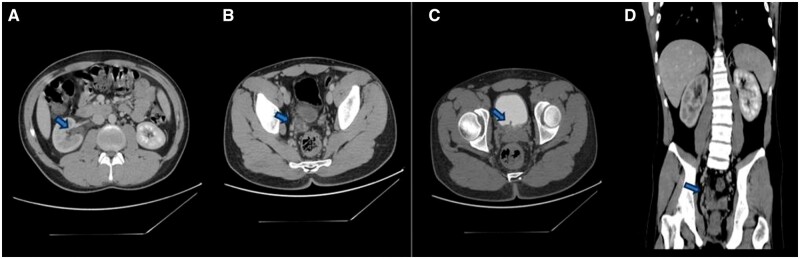

类蚓蛔虫是影响人类的最著名的寄生虫之一。蛔虫病在水、环境卫生和个人卫生不足的发展中国家流行,这些国家便于人与人之间的传播。在此报告中,我们报告了一个20岁男性的病例,他因严重的右侧疼痛,高烧和反复呕吐而到达急诊室。进行诊断评估,包括全血细胞计数测试、尿液分析、粪便分析、腹部超声和CT扫描。最终诊断为输尿管远端发现类蚓状瘤。输尿管镜检查证实了诊断并取出了蠕虫,该蠕虫长6厘米,呈棕色,并表现出紧密的弹性一致性。蛔虫通常在胃肠道中发现,但在尿道中出现是一种极其罕见的现象。在我们的病例中,最可能的解释是蛔虫通过逆行迁移进入输尿管远端,其中蛔虫从膀胱进入输尿管。

Ascaris lumbricoides is one of the most well-known helminthic parasites affecting humans. Ascariasis is prevalent in developing countries where inadequate water, sanitation, and hygiene facilitate human-to-human transmission. In this report, we present a case of a 20-year-old male who arrived at the emergency room with severe right flank pain, high-grade fever, and recurrent vomiting. Diagnostic evaluations were conducted, including a complete blood count test, urinalysis, stool analysis, abdominal ultrasound, and CT scan. The final diagnosis was A lumbricoides found in the distal part of the ureter. A ureteroscopy procedure confirmed the diagnosis and extracted the worm, which measured 6 cm in length, had a brown colour, and exhibited a tight elastic consistency. While Ascaris is commonly found in the gastrointestinal tract, its occurrence in the urinary tract is an extremely rare phenomenon. In our case, the most likely explanation is that the Ascaris accessed the distal ureter through retrograde migration, wherein the worm traverses from the bladder into the ureter.